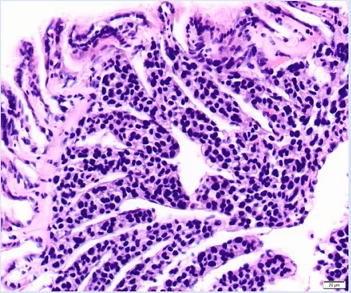

The detection of 1 hard clam with the new infectious disease, hemocytic neoplasia (HN), in 2020 highlights the need for continued vigilance and adaptation to prevent emerging disease outbreaks. The clam was imported from a New Jersey hatchery. The presence of a new disease in Long Island Sound underscores the importance of routine disease surveillance in Connecticut and acquiring health reports before shellfish are imported. HN is a relatively new disease and is consequently not well understood, but it is caused by cells that invade hard clam tissues, causing hemocytes to become non-functional (Roger Williams University 2021). Therefore, HN is an infectious disease that can be transmitted between hard clam populations (Smolowitz 2021). Some areas are already experiencing mass hard clam mortality events due to HN, such as in Wellfleet, MA; however, this disease is predominately believed to impact hatchery hard clams and it is unknown how far the infectious cells can be transported (Smolowitz 2021). HN was first detected in cultured hard clams in Wellfleet Bay starting in 2009 and has subsequently spread throughout the harbor (Smolowitz 2021). Hard clams that are collected on the surface tend to be positive and have a more advanced stage of HN than clams that are in the sediment (Smolowitz 2021). This form of neoplasia is related to neoplastic diseases in other bivalves but is distinct (Smolowitz 2021). There is no treatment, but clams with low infection levels are able to survive and produce disease-resistant offspring, which is occurring in Wellfleet, MA (Smolowitz 2021).

Hemocytic neoplasia in hard clam tissue. Photo by Dr. Smolowitz (all rights reserved).